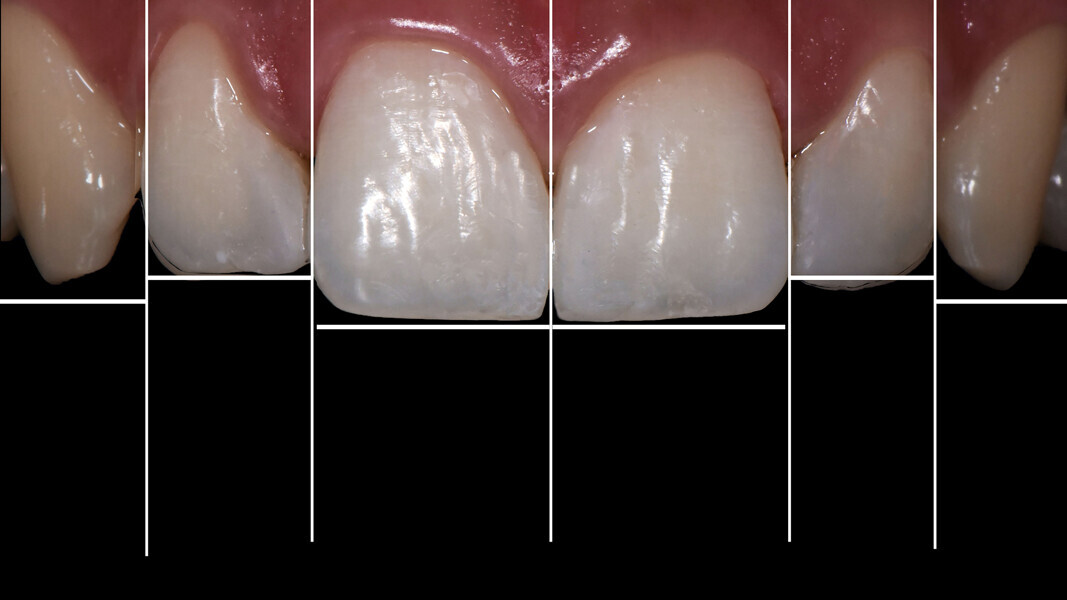

We followed a thorough analysis of the chromatic spectrum, as described by Naorungroj, to accurately and precisely establish the shades to be used in the operative steps (Fig. 2).1 The photographic material was carefully analysed to determine the ideal work planes to gain the information required to achieve the ultimate aesthetic aim of the treatment.

Figs. 2a–d: Choice of shade values.

Fig. 2b

Fig. 2c

Fig. 2d